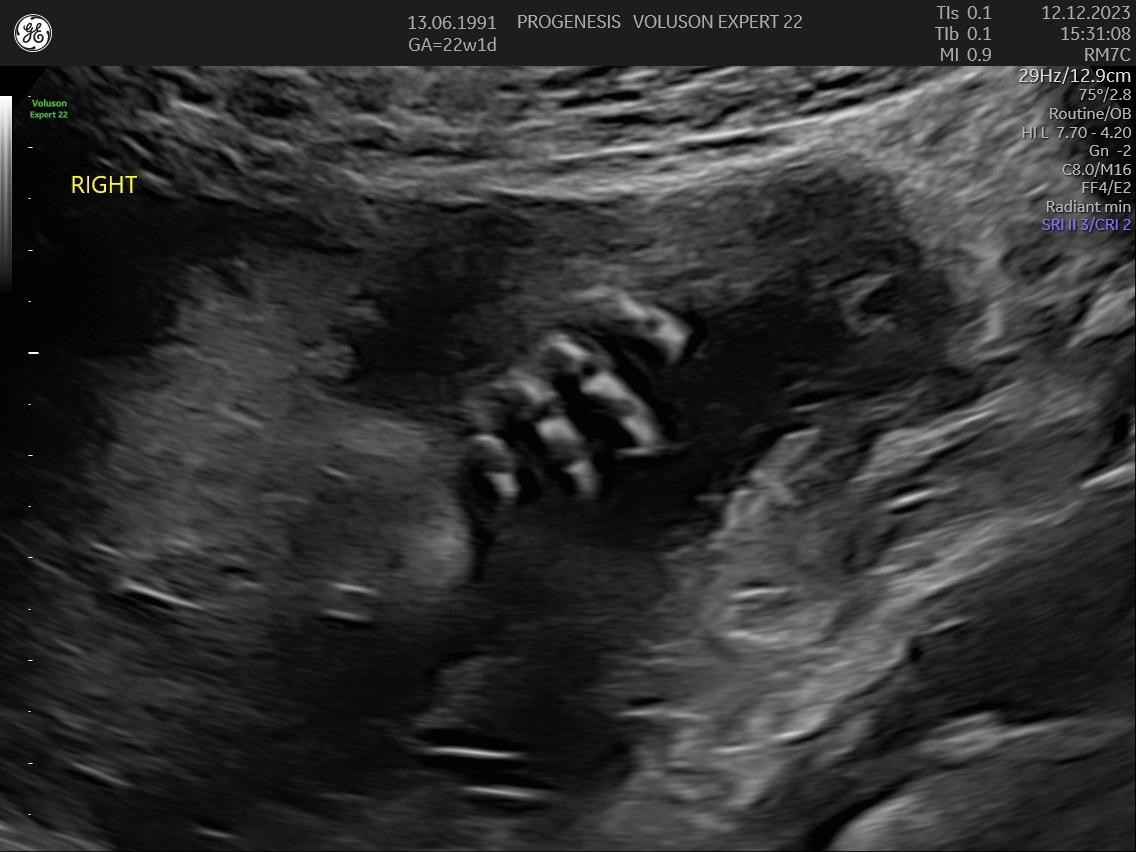

α) Η λεπτομερής αξιολόγηση της εμβρυϊκής ανατομίας, όπου αναγνωρίζονται τυχόν ανατομικές ανωμαλίες.